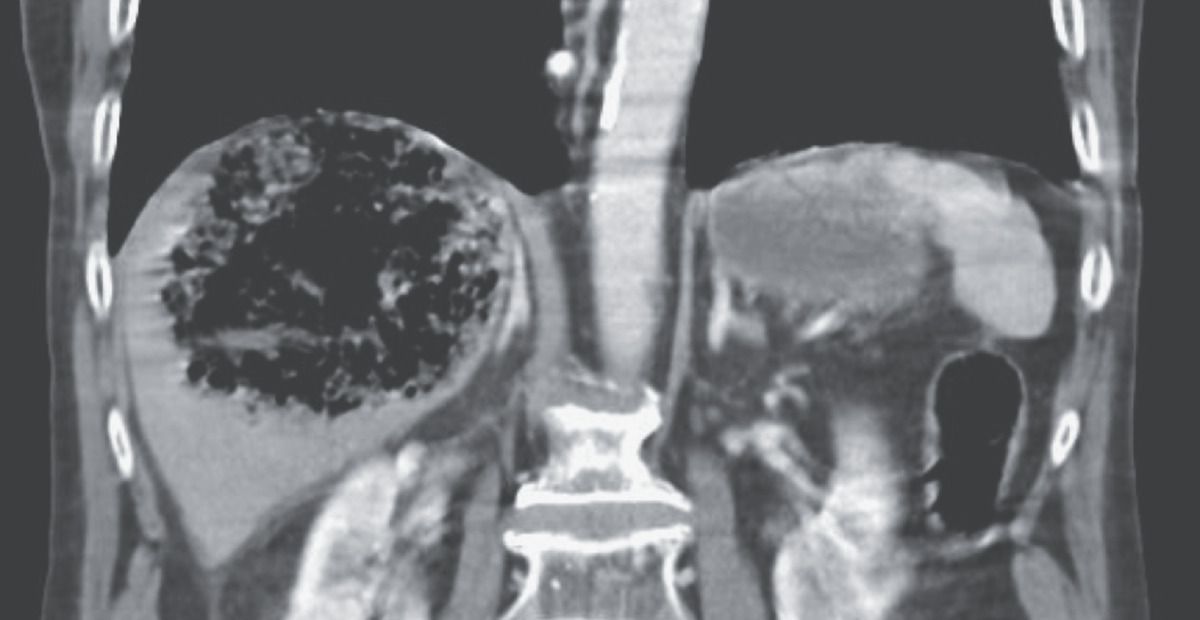

An 82-year-old man with diabetes, chronic pancreatitis, and biliary strictures presented to the emergency department with a 1-day history of fever and confusion. The heart rate was 150 beats per minute, and the blood pressure was 90/50 mm Hg. On physical examination, he was disoriented, and the right upper quadrant of the abdomen was tender to palpation. The white-cell count was 14,900 per cubic millimeter (reference range, 4000 to 11,000), the aspartate aminotransferase level 1380 units per liter (reference range, 5 to 40), and the alanine aminotransferase level 1121 units per liter (reference range, 5 to 40). A computed tomographic scan of the abdomen obtained after the intravenous administration of contrast material showed a large area of gas in the right hepatic lobe, a finding suggestive of emphysematous hepatitis. Treatment with broad-spectrum antibiotics was initiated, and the patient was admitted to the medical intensive care unit (ICU). A percutaneous hepatic drain was inserted. Blood and fluid cultures grew extended-spectrum beta-lactamase Klebsiella pneumoniae. Emphysematous hepatitis is a rare and fulminant infection of the liver parenchyma that can be seen in patients with diabetes. Despite continued care in the ICU, the patient’s condition deteriorated, and he died on day 8 of hospitalization.